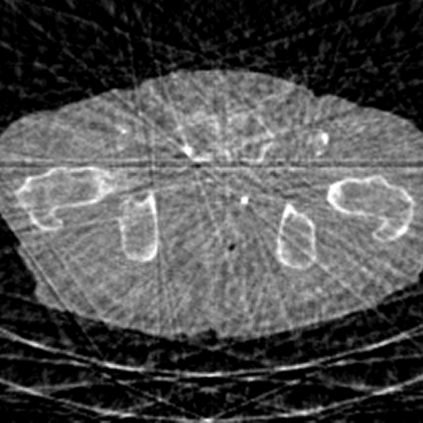

Sparse-view computed tomography (CT) -- using a small number of projections for tomographic reconstruction -- enables much lower radiation dose to patients and accelerated data acquisition. The reconstructed images, however, suffer from strong artifacts, greatly limiting their diagnostic value. Current trends for sparse-view CT turn to the raw data for better information recovery. The resultant dual-domain methods, nonetheless, suffer from secondary artifacts, especially in ultra-sparse view scenarios, and their generalization to other scanners/protocols is greatly limited. A crucial question arises: have the image post-processing methods reached the limit? Our answer is not yet. In this paper, we stick to image post-processing methods due to great flexibility and propose global representation (GloRe) distillation framework for sparse-view CT, termed GloReDi. First, we propose to learn GloRe with Fourier convolution, so each element in GloRe has an image-wide receptive field. Second, unlike methods that only use the full-view images for supervision, we propose to distill GloRe from intermediate-view reconstructed images that are readily available but not explored in previous literature. The success of GloRe distillation is attributed to two key components: representation directional distillation to align the GloRe directions, and band-pass-specific contrastive distillation to gain clinically important details. Extensive experiments demonstrate the superiority of the proposed GloReDi over the state-of-the-art methods, including dual-domain ones. The source code is available at https://github.com/longzilicart/GloReDi.